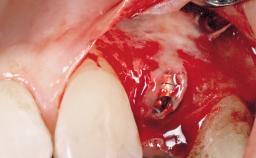

A 33-year-old female patient presented with an upper left central incisor that required extraction after a failed endodontic therapy. The tooth had been traumatized when the patient was a teenager and had undergone several endodontic treatments, including two apicectomy procedures. The patient was in good health and did not smoke. Clinical examination showed that the patient had a high lip line. In full smile, the gingival margins of the upper teeth were visible to the first molars. The gingival margins of central incisors 11 and 21 were only just showing. Examination of tooth 21 confirmed that the tooth was mobile and had hypererupted by 1 mm.

Placement Protocol Immediate implant placement

Socket Integrity Damage to one or more bone walls

Bone Volume Damage to one or more socket walls

Complexity Moderate

Risk of Complications High